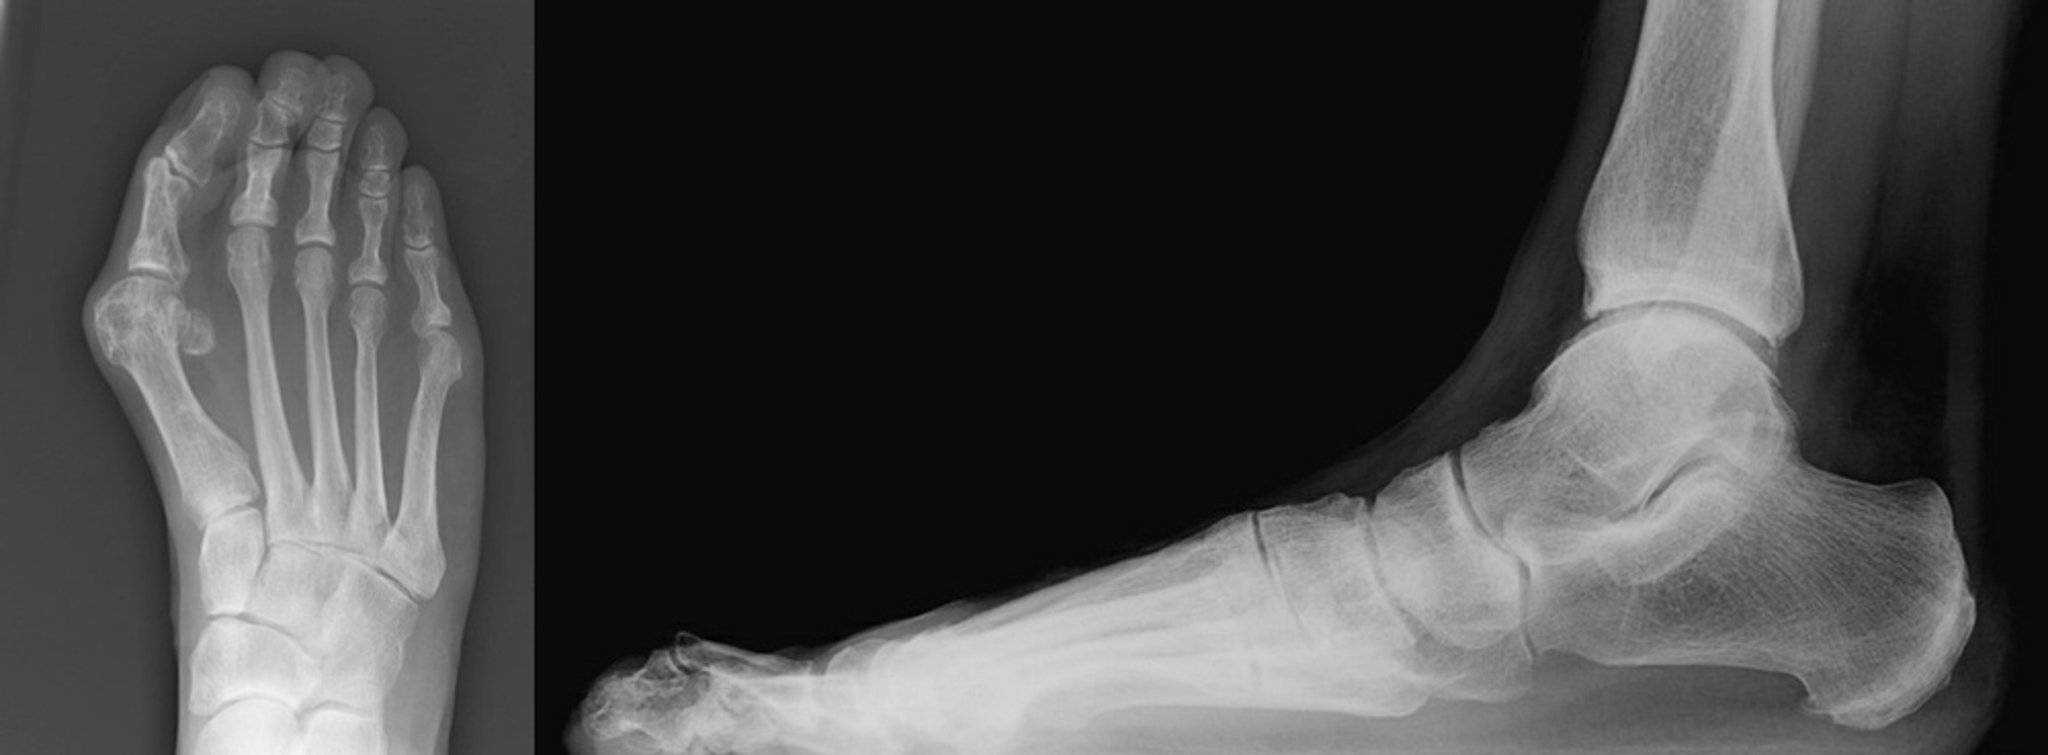

Рентгенограмма вальгусной деформации большого пальца стопы с молоткообразной деформацией

В переднезадней и боковой проекциях показаны вальгусная деформация большого пальца стопы с молоткообразной деформацией второго пальца стопы. На переднезадней проекции выявляется выраженная вальгусная деформация большого пальца стопы с медиальным отклонением первой плюсневой кости. Видно, как большой палец стопы опирается на второй палец. Второй палец отклонен латерально с сужением второго плюснефалангового сустава (слева). Латеральная проекция показывает второй дислоцированный в плюснефаланговом суставе палец. Показаны гиперэкстензия проксимального межфаланогового сустава и гиперэкстензия дистального межфалангового сустава второго пальца стопы (справа).